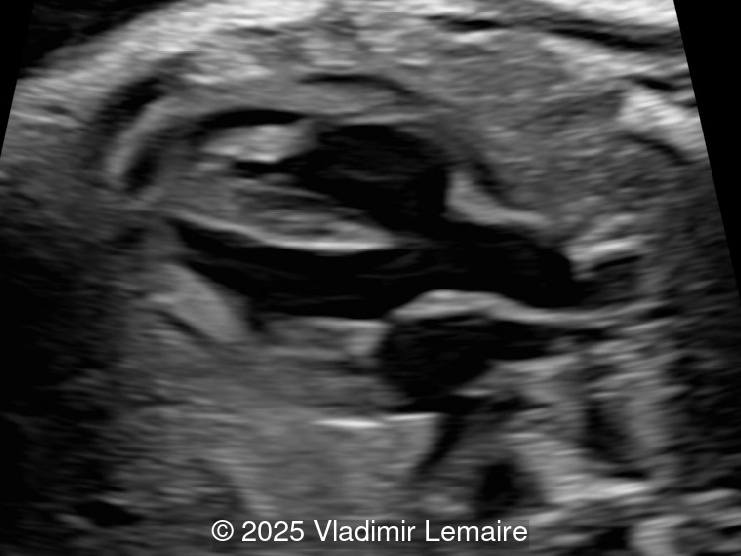

- Images 3 and 4: The five-chamber view shows the ventricular septal defect and the dilated overriding aorta.

In Tetralogy of Fallot, the four-chamber view typically appears normal unless a large ventricular septal defect is visible in this plane. TOF is usually detected in the left ventricular outflow tract view, which demonstrates a perimembranous, subaortic ventricular septal defect with an overriding aorta. The overriding aorta is due to the discontinuity between the interventricular septum and medial wall of the aorta (malalignment VSD). This results in a partial connection of the aorta to the right ventricle, with an aorta that is slightly shifted to the right, referred to as aortic dextroposition. The aortic root appears dilated, especially in the third trimester, because it receives blood from both the right and left ventricles. The overriding aorta has a parallel course to the interventricular septum in contrast to the ascending aorta in a normal heart.

Color Doppler confirms the presence of an overriding aorta with blood draining from both ventricles, through the ventricular septal defect into the aortic root. Due to high perfusion, inflow into the aorta appears aliased. At the level of the three-vessel-trachea view, color Doppler can also demonstrate a small pulmonary artery. Flow is antegrade across the ductus arteriosus in mild Tetralogy of Fallot and can be reversed in severe cases. Color Doppler can help differentiate various subgroups of TOF as postnatal ductal dependency of the pulmonary circulation can be associated with cyanosis of the newborn.